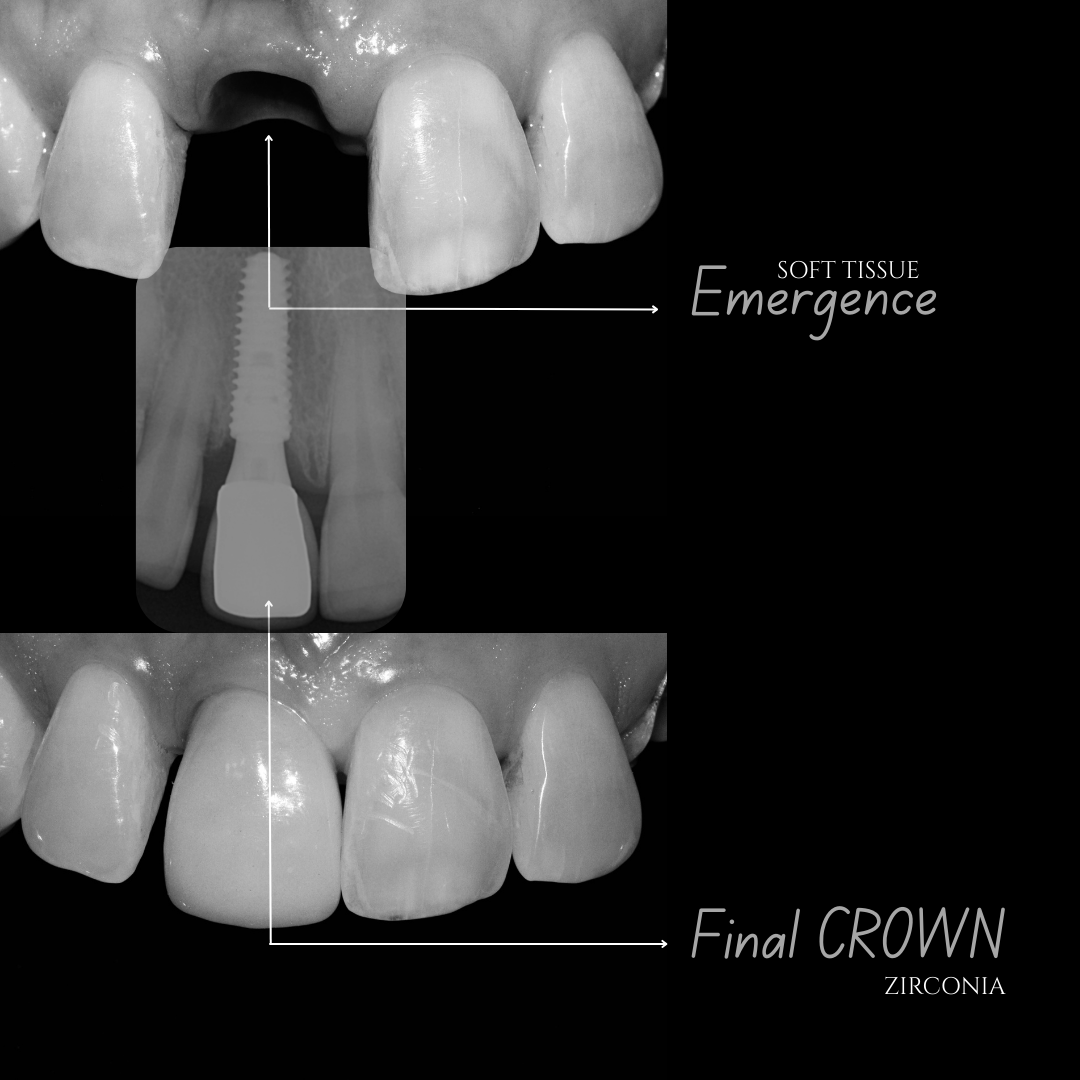

| Crown (Zirconia/Porcelain) | ₹6,000 – ₹15,000/- |

Dental implants are artificial tooth roots made of biocompatible titanium placed into the jawbone to replace missing teeth. They function like natural teeth and provide a strong foundation for crowns or bridges.

Our clinic uses advanced digital implant dentistry, guided by one of Pune's top expert dentists, including CBCT 3D scans, intraoral scanners, and precision-guided planning to ensure accurate implant placement, faster healing, and predictable results.